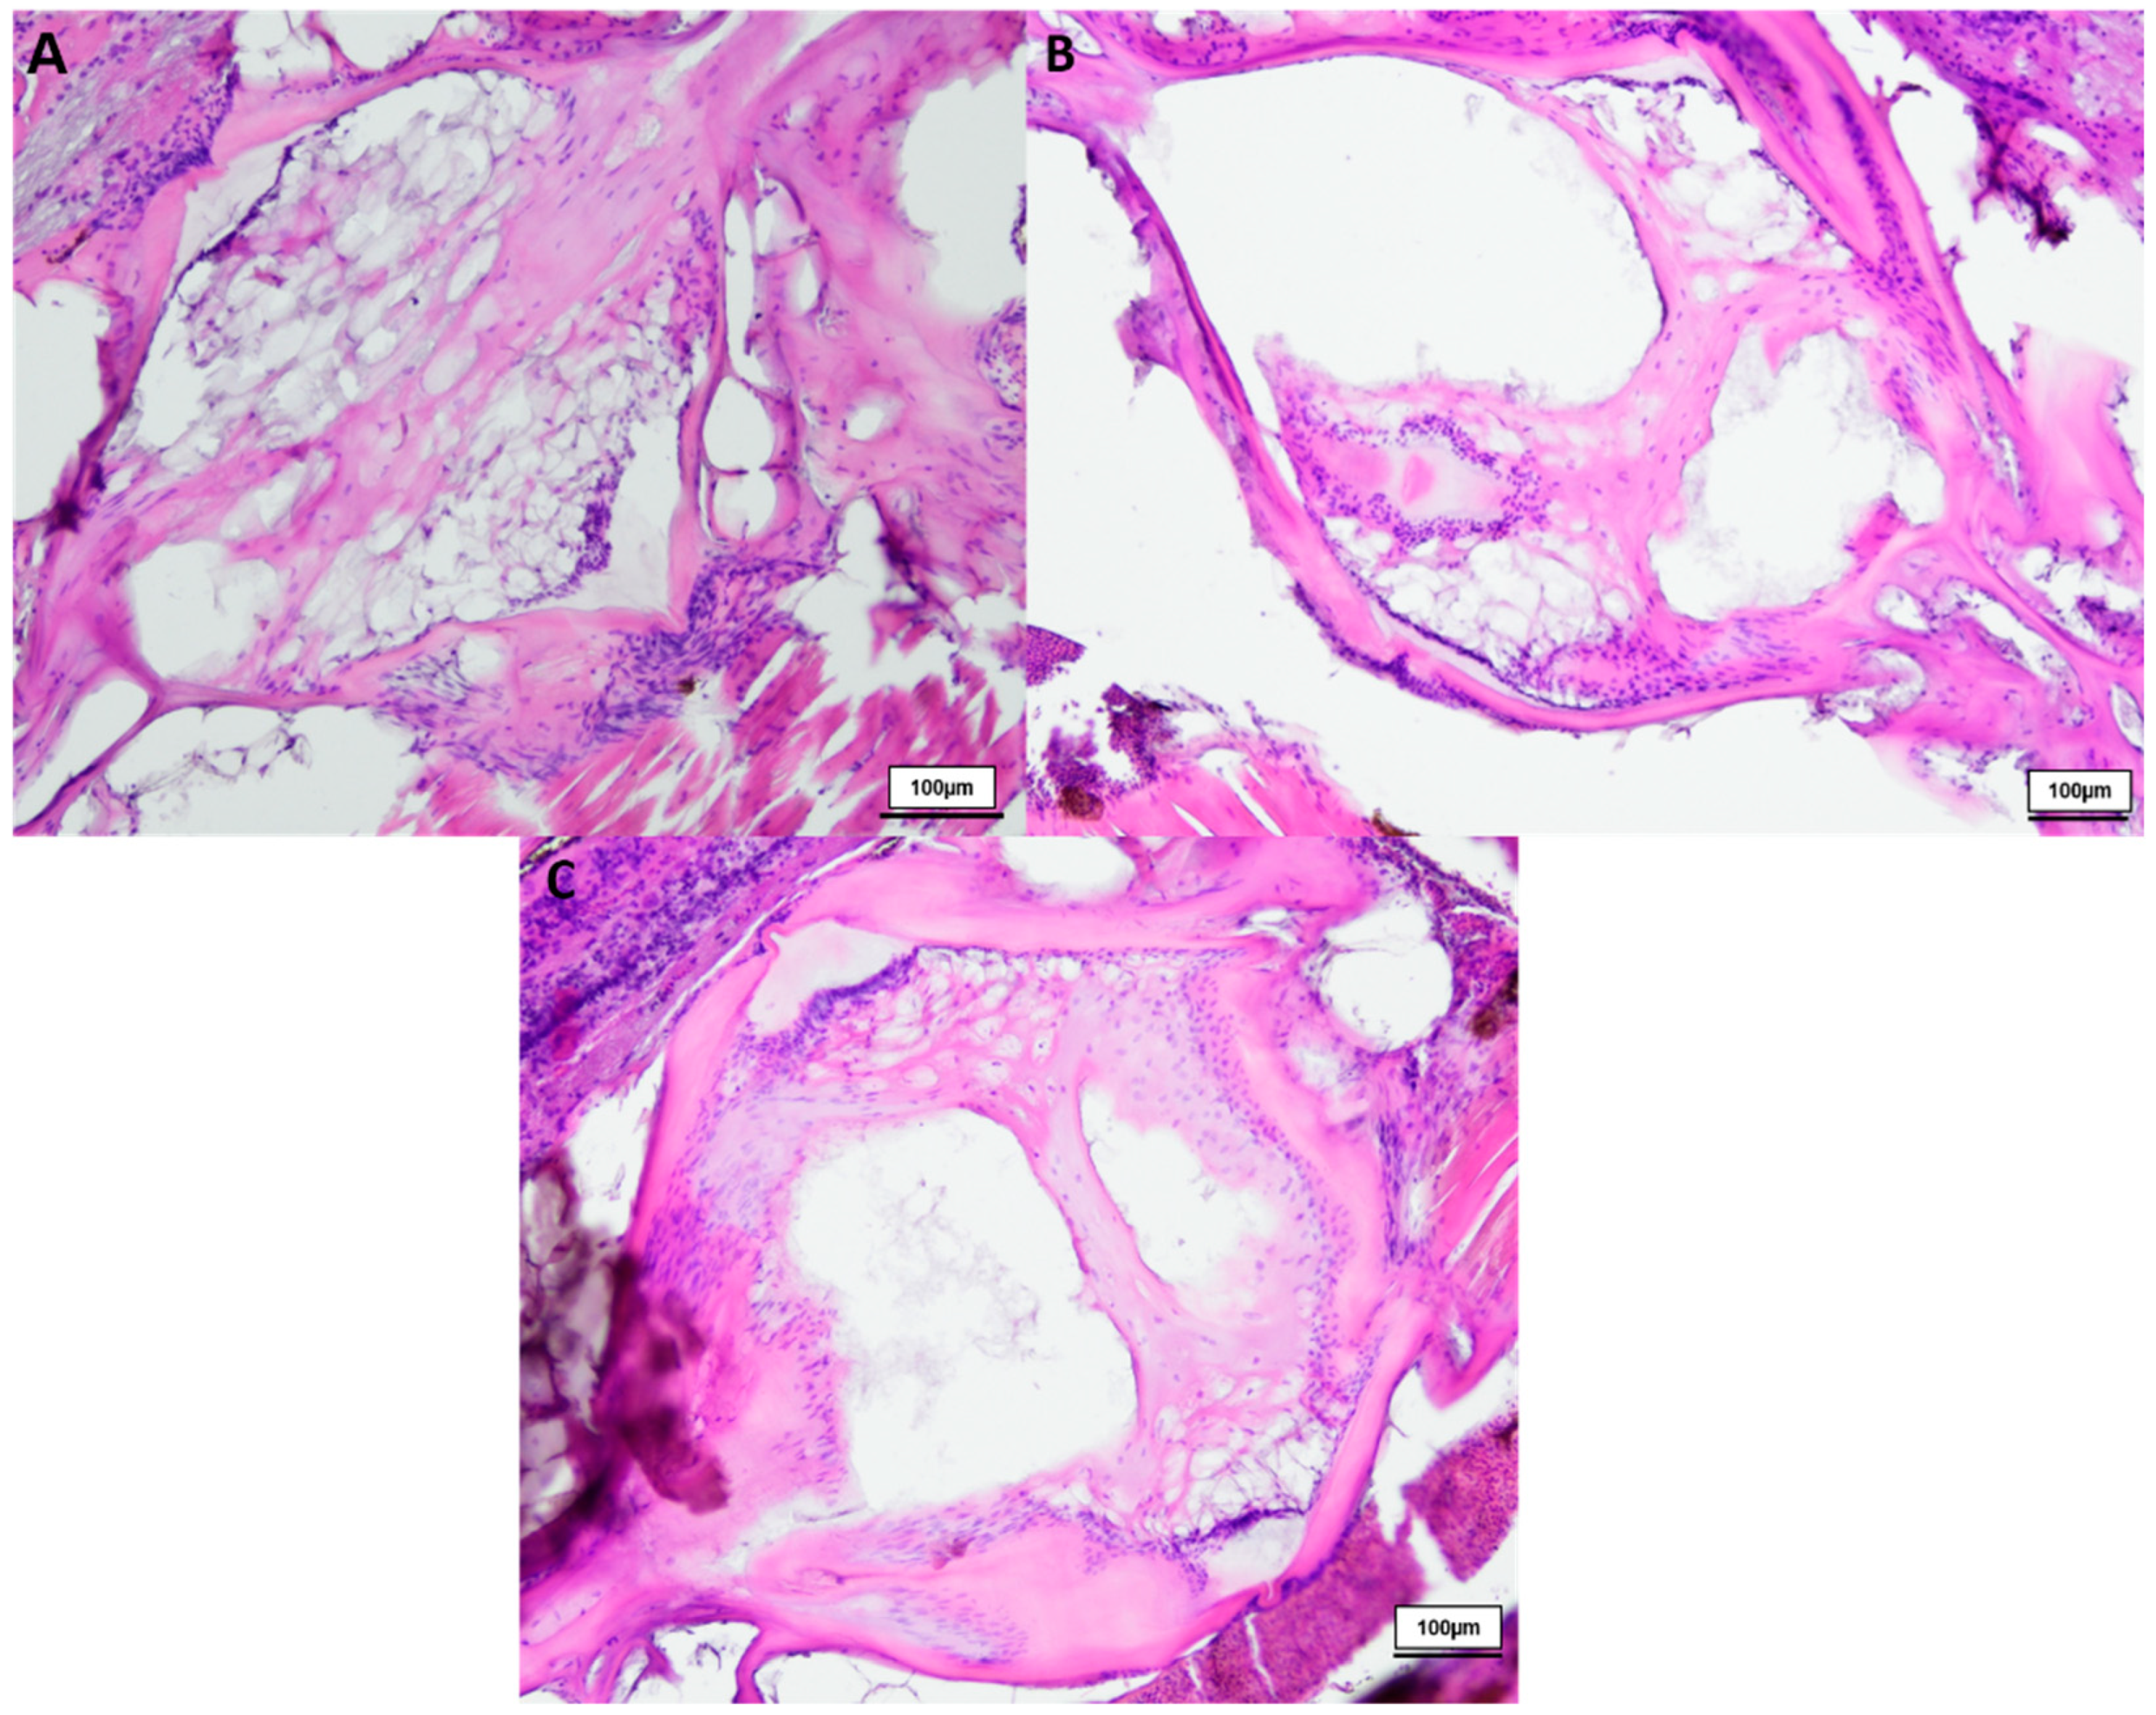

3. Results